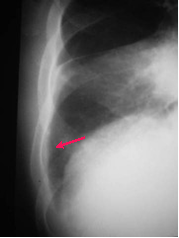

Laminar Effusion

A laminar effusion collects

between the lung and the

visceral pleura in the loose

connective tissue of the

subpleural space

Laminar effusions are

usually seen with CHF or

lymphangitic spread of

tumor